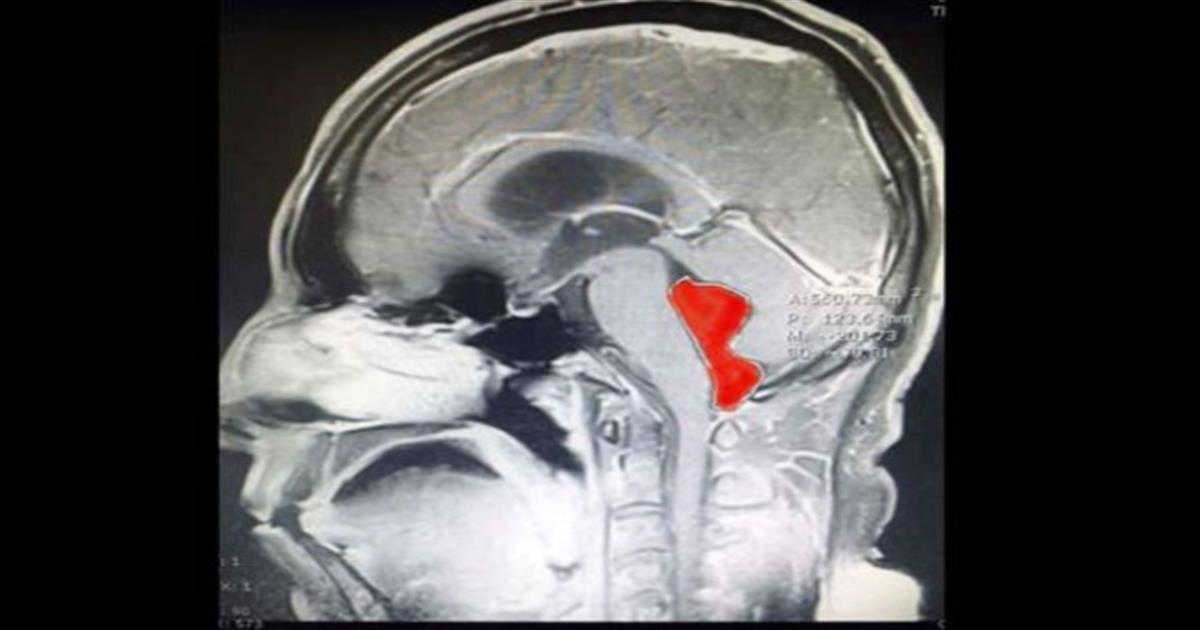

Η μαγνητική υπέδειξε μια κύστη στην τέταρτη κοιλία, πίσω από τον προμήκη μυελό και τη γέφυρα. Το ιατρικό team του κέντρου Ascension Seton του Τέξας ανάλαβε τη δύσκολη επέμβαση, καθώς η κύστη αποδείχτηκε τελικά πως ήταν το παρασιτικό σκουλήκι ταινία, μήκους 4-5 εκατοστών.

Το οποίο ήταν εκεί «τουλάχιστον 10 χρόνια». Ο Dr Jordan Amadio του Ascension Seton θεωρεί πως η ταινία πέρασε από μολυσμένη με αυγά ταινίας τροφή στον εγκέφαλο του Gerard, όπως αναφέρεται ο ασθενής (χωρίς επίθετο).

Ο Gerard επέστρεψε τελικά στη ζωή του, τη δουλειά και την οικογένειά του. Ο Amadio δήλωσε πως η επιτυχία ήταν ομαδική δουλειά.

«Είναι πάντα πρόκληση να μπορείς να αφαιρέσεις μια επιβλαβή πληγή από τον εγκέφαλο ασθενούς και να βλέπεις τόσο εξαιρετικό αποτέλεσμα», δήλωσε χαρακτηριστικά.